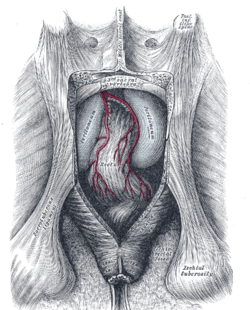

The superficial branches of the internal pudendal artery.

The posterior aspect of the rectum exposed by removing the lower part of the sacrum and the coccyx.